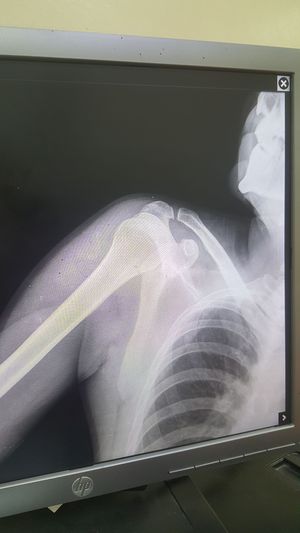

Clavicle fracture

Fracture

Clavicle